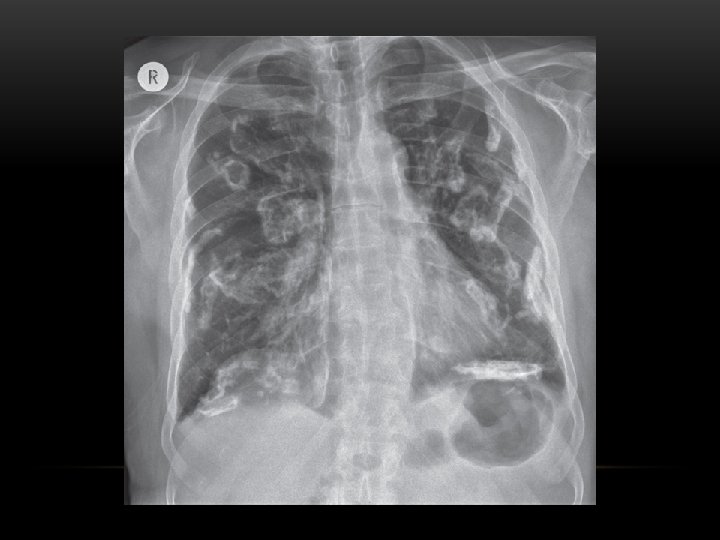

pleural masses Multiple • Pleural metastases. • Asbestos related pleural disease: Look for calcifications. • Malignant mesothelioma. Solitary • Pleural metastases: • Solitary fibrous tumor of the pleura. • Lipoma. • Malignant mesothelioma:

Multiple pulmonary, and pleural metastasis